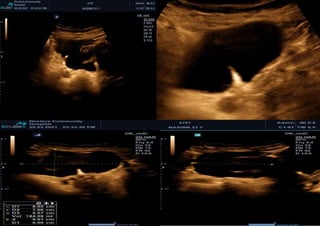

• IOTA descrition – Unilocular, unilocular-solid, multilocular, multilocular-solid or solid

–

Cyst contents – anechoic, low level, ground glass, hemorrhagic or mixed –

Uncertain (NO BENIGN RULES AND NO MALIGNANT RULES = UNCERTAIN

Example 3

Simple rules:UNCERTAIN

Borderline ovariantumour

Serous cystadenofibroma